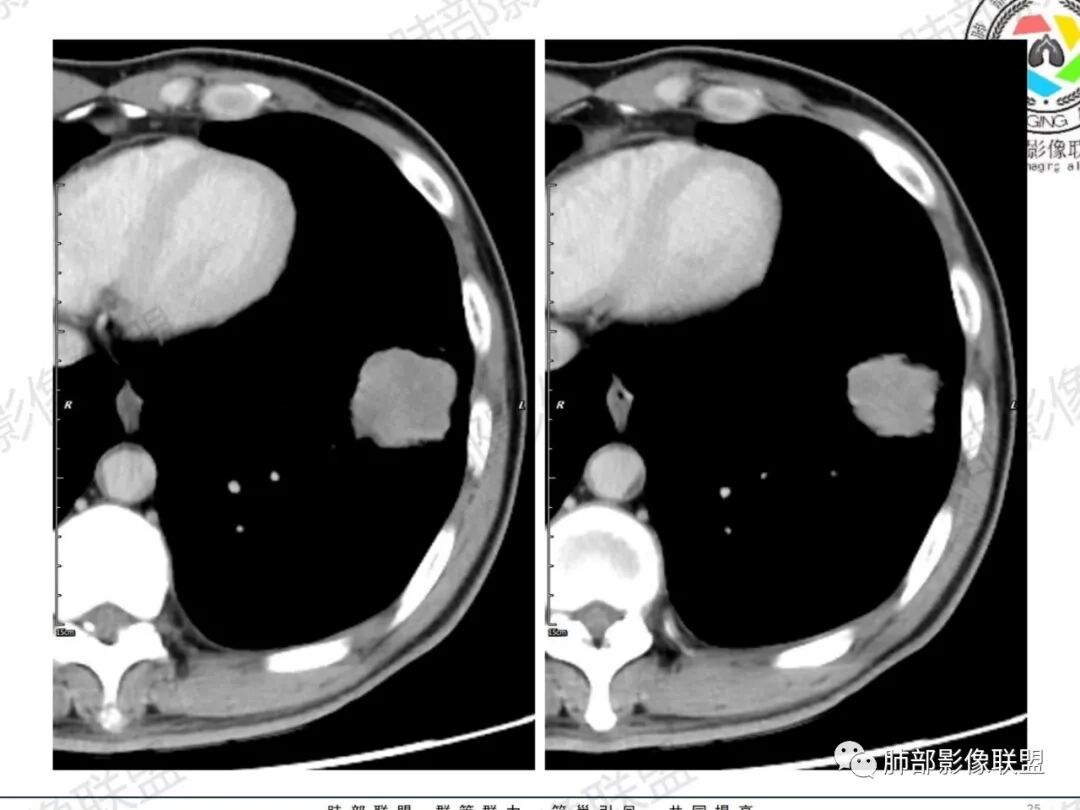

一切∮随缘:左肺下叶不规则肿块,边缘光滑,平直,局部彭隆,分叶,近端支气管堵塞,远端与胸膜相贴,平扫密度尚均匀,增强后不均匀强化,内部可见低密度坏死,胸膜下多发肺气肿,伴双肺散在光滑小结节,实验室肿瘤标志物高,考虑恶性:神经内分泌癌(大细胞),腺癌,鳞癌。

琦遇:恶性没有问题,肺气肿底子、病灶分叶、少许毛刺、叶间胸膜凹陷、部分边缘可见清晰的GGO、胸膜牵拉凹陷、局部胸水、近端支气管截断、部分支气管被推移、占位效应明显、强化特点为不均匀强化、内部有少许沼泽样低强化区,强化部分轻中强化为主、余肺可见转移性结节、左肺上叶似为囊腔型腺癌一枚,肿瘤标志物提示非小、神经内分泌,综合分析考虑大神泌、腺癌、腺鳞癌、鳞癌  同时左肺上叶囊腔型腺癌  肺转移

飞鹰行动:中年人,男性,胸疼入院,左肺下叶占位,张力较高,边界可见分叶,局部可见明显收缩性改变,增强病灶内部有延迟强化表现,考虑恶性病变,大细胞癌伴肺内转移或者囊腔样腺癌伴转移。

傅昌瑜:中老年男性,肺气肿背景,右胸背疼痛1周。CEA、NSE、CYFRA—211升高。左上肺混合磨玻璃结节,内见较多空泡和扩张支气管。左下肺胸膜下肿块,边缘较光滑,深分叶,似有血管进入,与支气管关系不清,内见不均匀强化,见沼泽地样坏死,有胸膜栽赃。另两肺多发圆形小结节。考虑恶性并肺内转移,多原发可能性大,左上肺腺癌,左下肺病理难以判断,小细胞癌?鳞癌?

小锁:中老年男性,肺气肿背景,右胸背疼痛1周。CEA、NSE、CYFRA—211升高。左上肺混合磨玻璃结节,边界清楚,内见较多空泡。左下肺肿块,边缘清楚,深分叶,有血管和支气管进入,胸膜凹陷。另两肺多发圆形小结节。考虑双发原位癌,左上肺腺癌,左下肺大神泌或腺鳞癌可能,肺内转移。

蓝天白云:中年男性,肺气肿背景,左肺下叶肿块,边缘膨隆,有分叶,内有湖泊样坏死,有轻中度强化,局部胸膜栽赃,收缩力不强,周围见肺气肿征象。左肺上叶混合磨玻璃影,边界清楚,考虑都是恶性,左上肺iac,左下肺腺鳞癌,或大细胞肺癌可能。两肺多发结节,考虑转移

毛勤香:老年男性,肺气肿背景,左肺下叶肿块,分叶,边缘光滑,土豆块样,细支气管闭塞,增强轻度不均匀强化,似有坏死,左肺另见多发结节,淋巴结未见明显肿大,恶性确定,吸烟史,鳞癌破坏力强,侵袭力差,多原发的一般很少多于3个,故排后,首先考虑神经内分泌癌,局部血管穿行,鉴别淋巴瘤

周太狼:中年男性,吸烟、高血压史,肿瘤指标升高,肺气肿背景下,左肺下叶肿块影,分叶、膨隆、未跨叶裂,支气管截断,不均匀强化。另双肺多发结节及磨玻璃影,左肺上叶混合磨玻璃,内可见多发空泡影。整体考虑恶性,肺癌伴肺内转移,左下肺鳞癌?神经内分泌癌?左肺上叶囊腔腺癌?

LCNEC最常见的影像特征包括:(1)肿块发生部位:周围型肺癌为主,少数发生于肺中央。(2)肿块大小及形态。因肿瘤细胞生长迅速常形成较大肿块,因此其体积一般较大,直径常在3~10cm范围内,病灶常为不规则形软组织肿块。(3)肿块边界。多数学者报道大多数肿块边界清晰,边缘呈分叶状,毛刺征及“胸膜凹陷征”少见,认为与该病对周围组织浸润较轻及较少产生纤维瘢痕组织牵拉有关联。(4)肿块密度、强化特点及代谢情况。据文献报道,该类肿瘤因体积较大CT上常见软组织肿块,且多数密度不均匀,内见囊变坏死区,增强后呈轻或中度不均匀强化(可见强化者占75.7%),认为其强化特点与其内部肉眼可见坏死灶和肿瘤较大直径有关。(5)伴随症状及远处转移。该病恶性程度高,侵袭性强,常侵犯邻近结构,如胸膜、心包、邻近骨质或纵隔内组织等,易出现纵隔淋巴结转移,部分发生肺内及远处转移,少数早期可出现广泛远处转移。